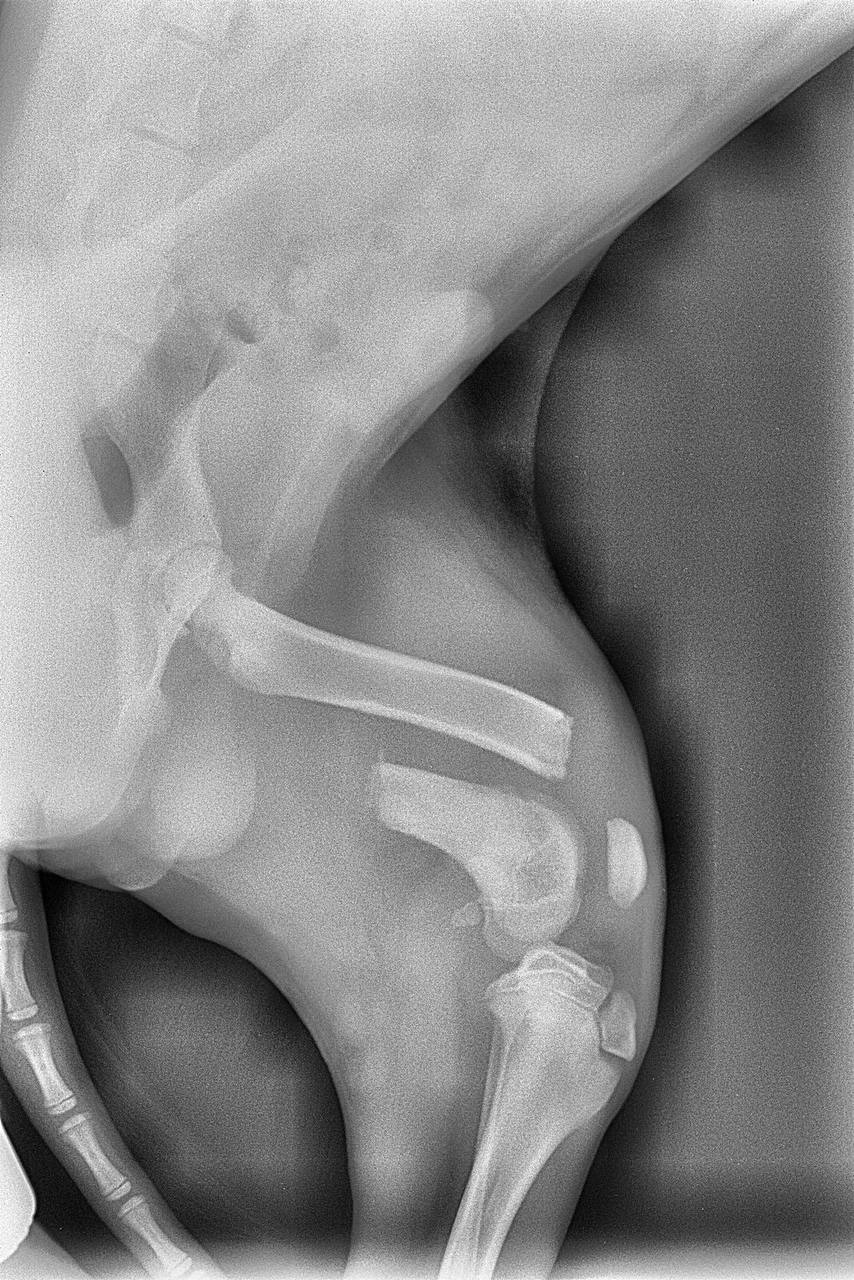

Здравствуйте,прошу откликнуться.В сентябре подобрала собачку,с поломанной лапой,сделали операцию,было смещение.Очень долго не срастался перелом.После сняли конструнцию,но около месяца назад Снова перестал становиться на лапу и сильный отек.Так как в клинике за операцию у меня все еще долг нас не примут больше,я внесла сумму 40 тысяч а долг около 20 ти еще. Предварительно нам озвучили что вероятнее всего нужно ампутировать лапу.Прошу вас кто может забрать собаку,что бы ее спасти,я не смогу сейчас осилить растраты,хоть и очень к нему привязались.Он скулит ,почти перестал кушать,я понимаю что ему больно,но не могу помочь.Прошу заберите собаку так как я не в состоянии оплатить ему лечение,выбросить на улицу не могу,усыпить подло.